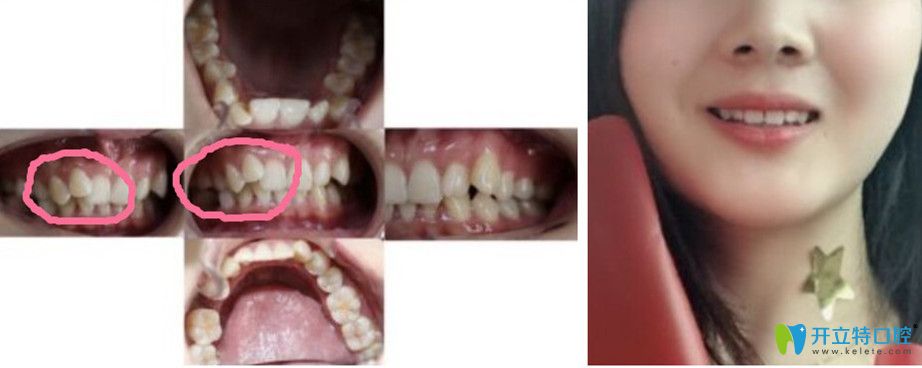

顧客評價:矯正真的會改變臉型,跟整容似的。矯正前有兩個虎牙,別人都說虎牙多好看啊不需要弄,可我的是那種突出來像暴牙,有一顆還是扣在里面的,不好看也并不可愛!沒矯正前是不太愛笑的。

▼虎牙在伊爾意矯正前后對比照,變化是不是很大

虎牙在伊爾意矯正前后對比照